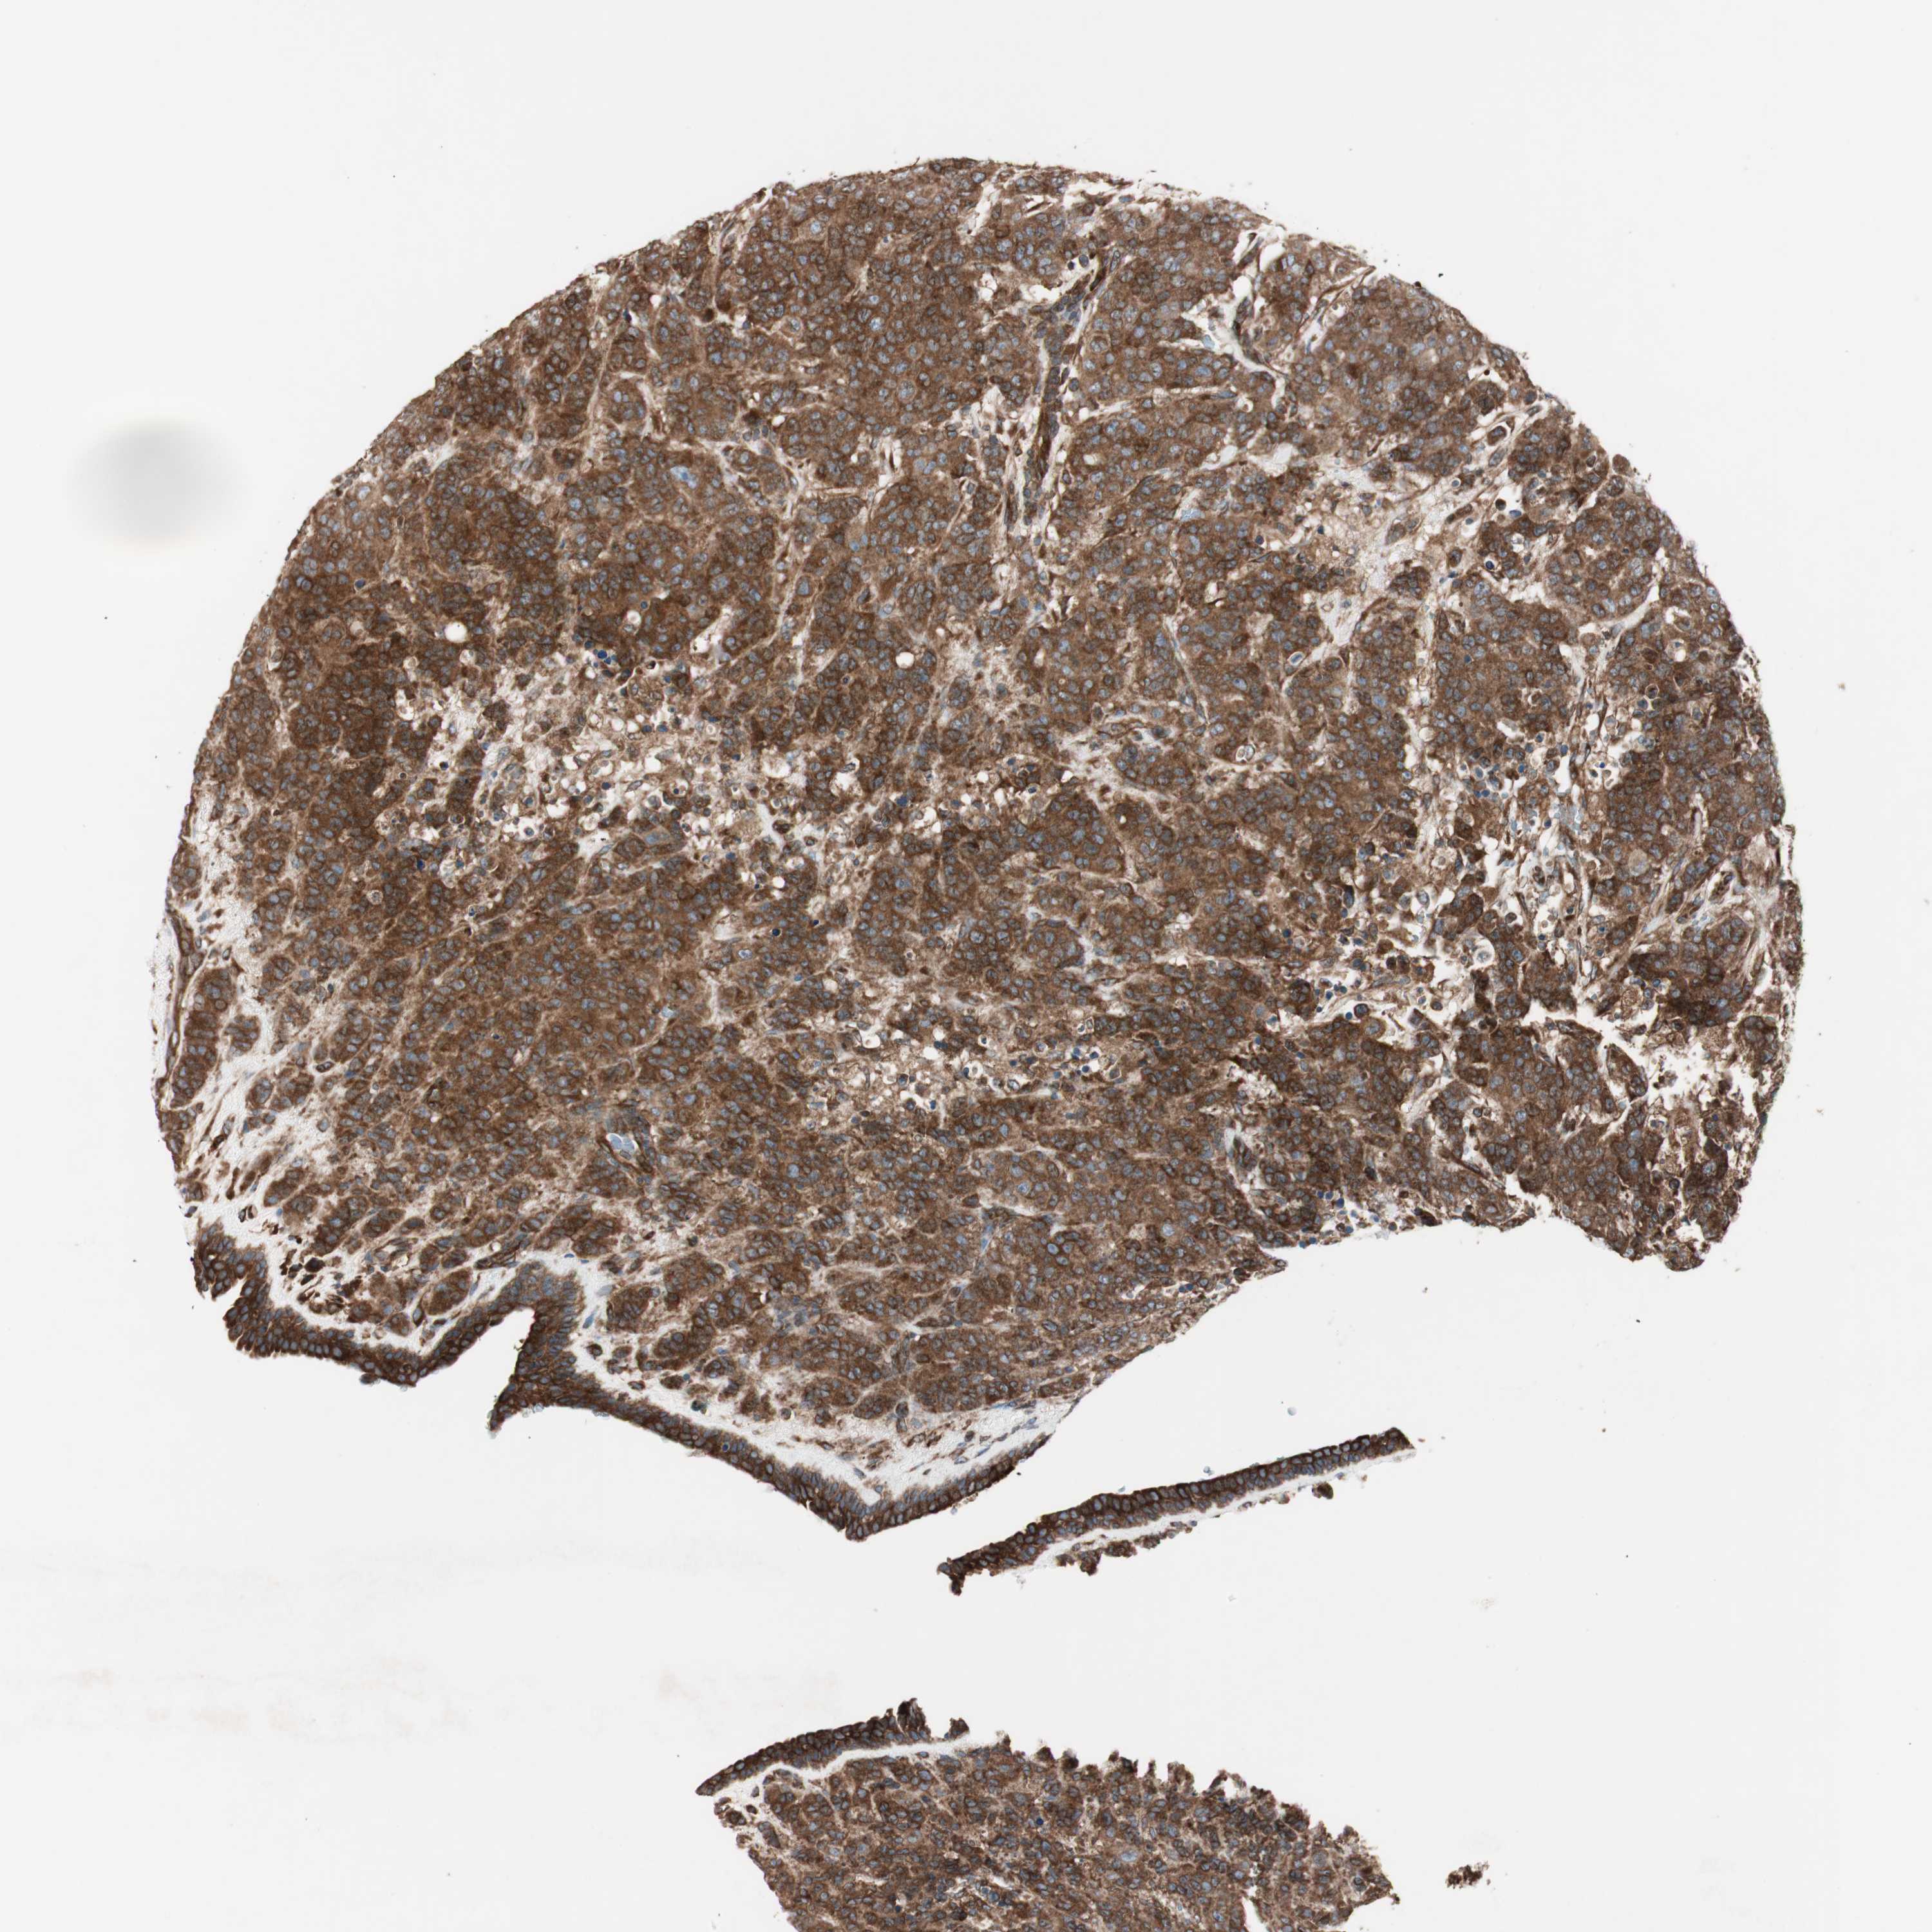

CANCER BREAST CANCER Show tissue menu

BRCA TCGA BRCA VALIDATION PROTEIN EXPRESSION

ANTIBODIES

AND

VALIDATION